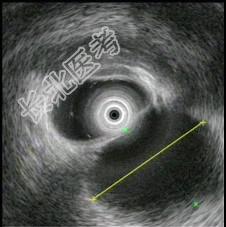

- 多项选择题1.超声内镜如图,B超引导穿刺检查示渗出液,淀粉酶265U/L。此患者的诊断 ( )

A、急性胰腺炎伴假性囊肿

B、慢性胰腺炎伴假性囊肿

C、胰腺囊腺癌